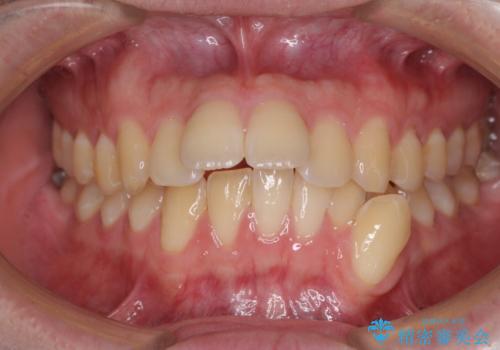

[ マウスピース矯正 ] 出っ歯に見える前歯を改善したい

![[ マウスピース矯正 ] 出っ歯に見える前歯を改善したいの症例 治療前](https://seimitsushinbi.jp/wp/wp-content/uploads/2023/10/IMG_6858-500x350.jpg?v=1697014973)

![[ マウスピース矯正 ] 出っ歯に見える前歯を改善したいの症例 治療後](https://seimitsushinbi.jp/wp/wp-content/uploads/2023/10/8a6c9bf89570c0c75da0a5fabd1cd70e-500x350.jpg?v=1697014858)